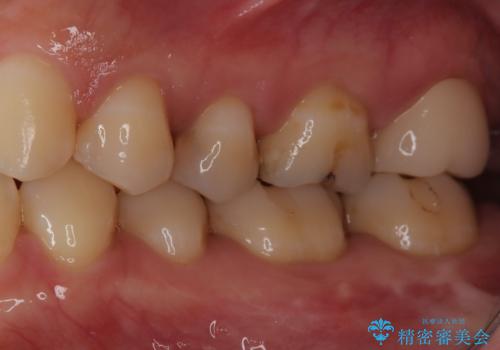

【セラミックインレー】虫歯の治療

- 定期検診にて虫歯を認めたため、セラミックインレーにて治療を行いました。

治療時にはラバーダムを装着しております。